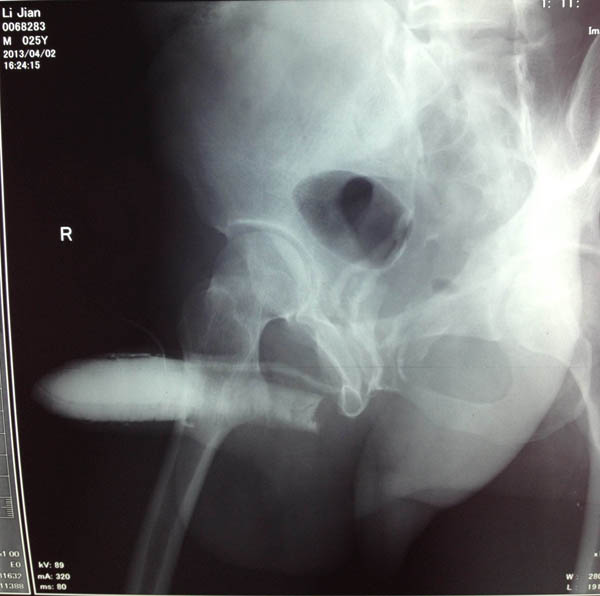

阴茎海绵体造影显示存在复杂的静脉漏

手术中